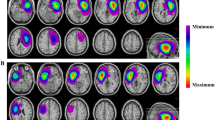

Transsylvian approach

A wide Sylvian fissure split is typically performed to obtain complete exposure of the insular region. Potts et al. [29] have recommend a two-part fissure split, divided into anterior and posterior segments. The anterior fissure split proceeds from distal to proximal, following cortical arteries to opercular arteries to the M2 segments at the base of the MCA bifurcation. This dissection exposes the anterior zone of the insula through several windows of MCA vessels. The posterior fissure split then proceeds from proximal to distal. This dissection becomes more difficult as the Sylvian cistern ends posteriorly and the frontal–temporal opercula become attached at their pial margins, as described in detail by Safaee et al. [30]. Due to constraints in space and surgical positioning, the posterior fissure split may require the assistance of fixed retraction or the sacrifice of superficial Sylvian veins (Fig. 2) [29, 31]. However, a key advantage of the transsylvian approach is the sparing of the frontal and temporal opercula in the dominant hemisphere, which minimizes the risk of direct surgical injury to the language network. In modern series, long-term neurological morbidity following the transsylvian approach for insular gliomas has ranged from 9 to 11% [2, 32].

The transsylvian approach requires meticulous subarachnoid dissection and direct manipulation of critical vasculature. For larger exposures, it may also require opercular retraction, which can compress the M3 branches and lead to frontal lobe ischemia [31, 32]. Conversely, the transcortical approach includes frontal and/or temporal corticectomies, necessitating the expertise and adding the risks of direct cortical stimulation techniques. Traditionally, the choice of transsylvian versus transcortical corridors has been based on historical practice at individual institutions or anecdotal experiences of individual surgeons. Recently, clinical and cadaveric studies have used insular glioma anatomy to inform a neurosurgeon’s decision as to which approach is associated with the lowest rate of neurological morbidity [2, 26, 31].

A recent retrospective study comparing both approaches in 100 consecutive patients reported that surgeons were more likely to choose the transcortical approach over the transsylvian approach for larger gliomas (p = 0.02) and for gliomas located in Zone III (p < 0.01) [2]. Further, for tumors located in Zone II, the transcortical approach was associated with a significantly lower incidence of tissue ischemia on postoperative MRI scans (p = 0.02). It was hypothesized that this was the result of excessive retraction of the frontal opercula or sacrifice of Sylvian vessels in order to gain adequate access to Zone II gliomas (Fig. 2). These results correlated with an anatomical analysis in cadaveric subjects by Benet et al. [31] in which the transcortical approach was associated with more surgical freedom to the posterior zones of the insula (Zones II and III) than the transsylvian approach. Additionally, the transsylvian approach to the posterior insula often required frontal lobe retraction and sacrifice of Sylvian veins for complete exposure, which was deemed unsafe in 30% of their cadaveric subjects. Thus, while both techniques are associated with an acceptable morbidity profile, the transcortical approach appears to be favored over the transsylvian approach for larger gliomas with significant posterior extension, as it provides a direct view to this insular region, preserves surgeon comfort, and maximizes surgical exposure (Fig. 3).